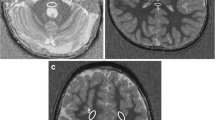

R2* values of the three grey nuclei are about the same in the youngest age group (CN 10.8 ± 0.5; GP 10.7 ± 0.7; PT 11.3 ± 0.5). The biggest increase of R2* does occur in the GP (Fig. 5) similar to the susceptibility values, although the change over time is much slower. R2* values do correlate highly significant (p < 0.001) with age (Pearson’s correlation coefficients: CN 0.695; GP 0.882; PT 0.611). For the age group 0–24 months, the CN R2* values change with a higher Pearson’s coefficient with respect to age (for CN Pearson’s R = 0.817, p < 0.001; for PT as well as GP R = 0.842, p < 0.001, respectively). The R2* values increase faster during this early time period and slower for later time points. The QSM values, on the other hand, increase slower or even decrease for this early time period but increase faster for later time points (Fig. 6).

Diagram showing the change of QSM and R2* values during the first 4 years of life within the ROI’s of GP, PT, and CN (Loess-curve fitting by SPSS). For GP (top row), R2* values do increase more rapidly during the first 2 years compared to the almost unchanged QSM values, suggesting a combined change of diamagnetic and paramagnetic effects in the tissue. For PT (middle row), R2* values also do increase more rapidly during the first two years compared to the QSM values, also suggesting a combined change of diamagnetic and paramagnetic effects in the tissue. QSM value increase occurs later compared to the GP. For CN (bottom row), R2* values again do increase more rapidly during the first 2 years compared to the QSM values. QSM values start to increase after 24 months of age, comparable to PT

We found very similar susceptibility values within the three tested deep nuclei in the youngest children of our cross-sectional cohort, which increased age-related more rapidly in the globus pallidus compared to the head of the caudate nucleus and the putamen leading to a recognizable difference at the age range of 50–100 months. Although our method is different to Ning et al., we found almost the same slope of the correlation between age and susceptibility in the globus pallidus. The increase of the QSM values of the putamen and caudate nucleus developed with almost the same slope, differing only by a slightly higher level of paramagnetic susceptibility in the caudate than in the putamen. Interestingly, the QSM values of the globus pallidus and putamen did start at a more negative susceptibility compared to the head of the caudate nucleus in our study, which is also in accordance with data published by Ning et al. [35]. The R2* values in our study showed similar changes with increasing age compared to data found by Ning et al. [26], but the slope of the R2* increase overall is smaller compared to the QSM data. This is completely different when looking at the age group 0–24 months. R2* values do increase more rapidly than the almost unchanged QSM values during this time span, indicating a mixed effect of increasing diamagnetic and paramagnetic susceptibility changes caused by a parallel development of myelination and iron deposition. After 2 years, the myelination process has usually finished and the ongoing iron deposition is indicated by the combined increase of QSM and R2* values.